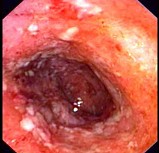

(单选题)肠镜检查如图,病理示固有膜内弥漫性淋巴细胞、浆细胞、单核细胞浸润,最可能的诊断为()。

A:Crohn病

B:肠结核

C:肠伤寒

D:梅克尔憩室

E:溃疡性结肠炎